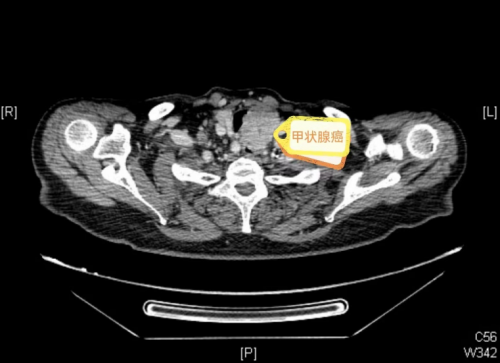

甲状腺彩超提示甲状腺肿块分类为5类,与气管关系密切,提示为恶性,入院后,复查增强CT检查提示甲状腺癌累及气管、食管壁,压迫气管达三分之二,电子鼻咽喉镜发现左侧声带麻痹。”据立博体育|实时赛事直播与比分|权威专家分析与体育竞猜平台

耳鼻咽喉头颈外科主任敬前程介绍,“这类甲状腺癌病情复杂,侵犯了喉返神经导致声带麻痹,又侵犯了气管、食管,手术难度大,并发症发生率很高,且患者年事已高,身体机能减退,合并有支气管哮喘、冠心病、高血压等多种基础疾病,围术期容易出现感染、血栓、心衰、呼衰、出血、电解质紊乱等并发症,可能导致生命危险。但如果不做手术,肿瘤继续增大将会进一步压迫气管,导致呼吸困难加重,因此尽快手术对患者来说至关重要。”